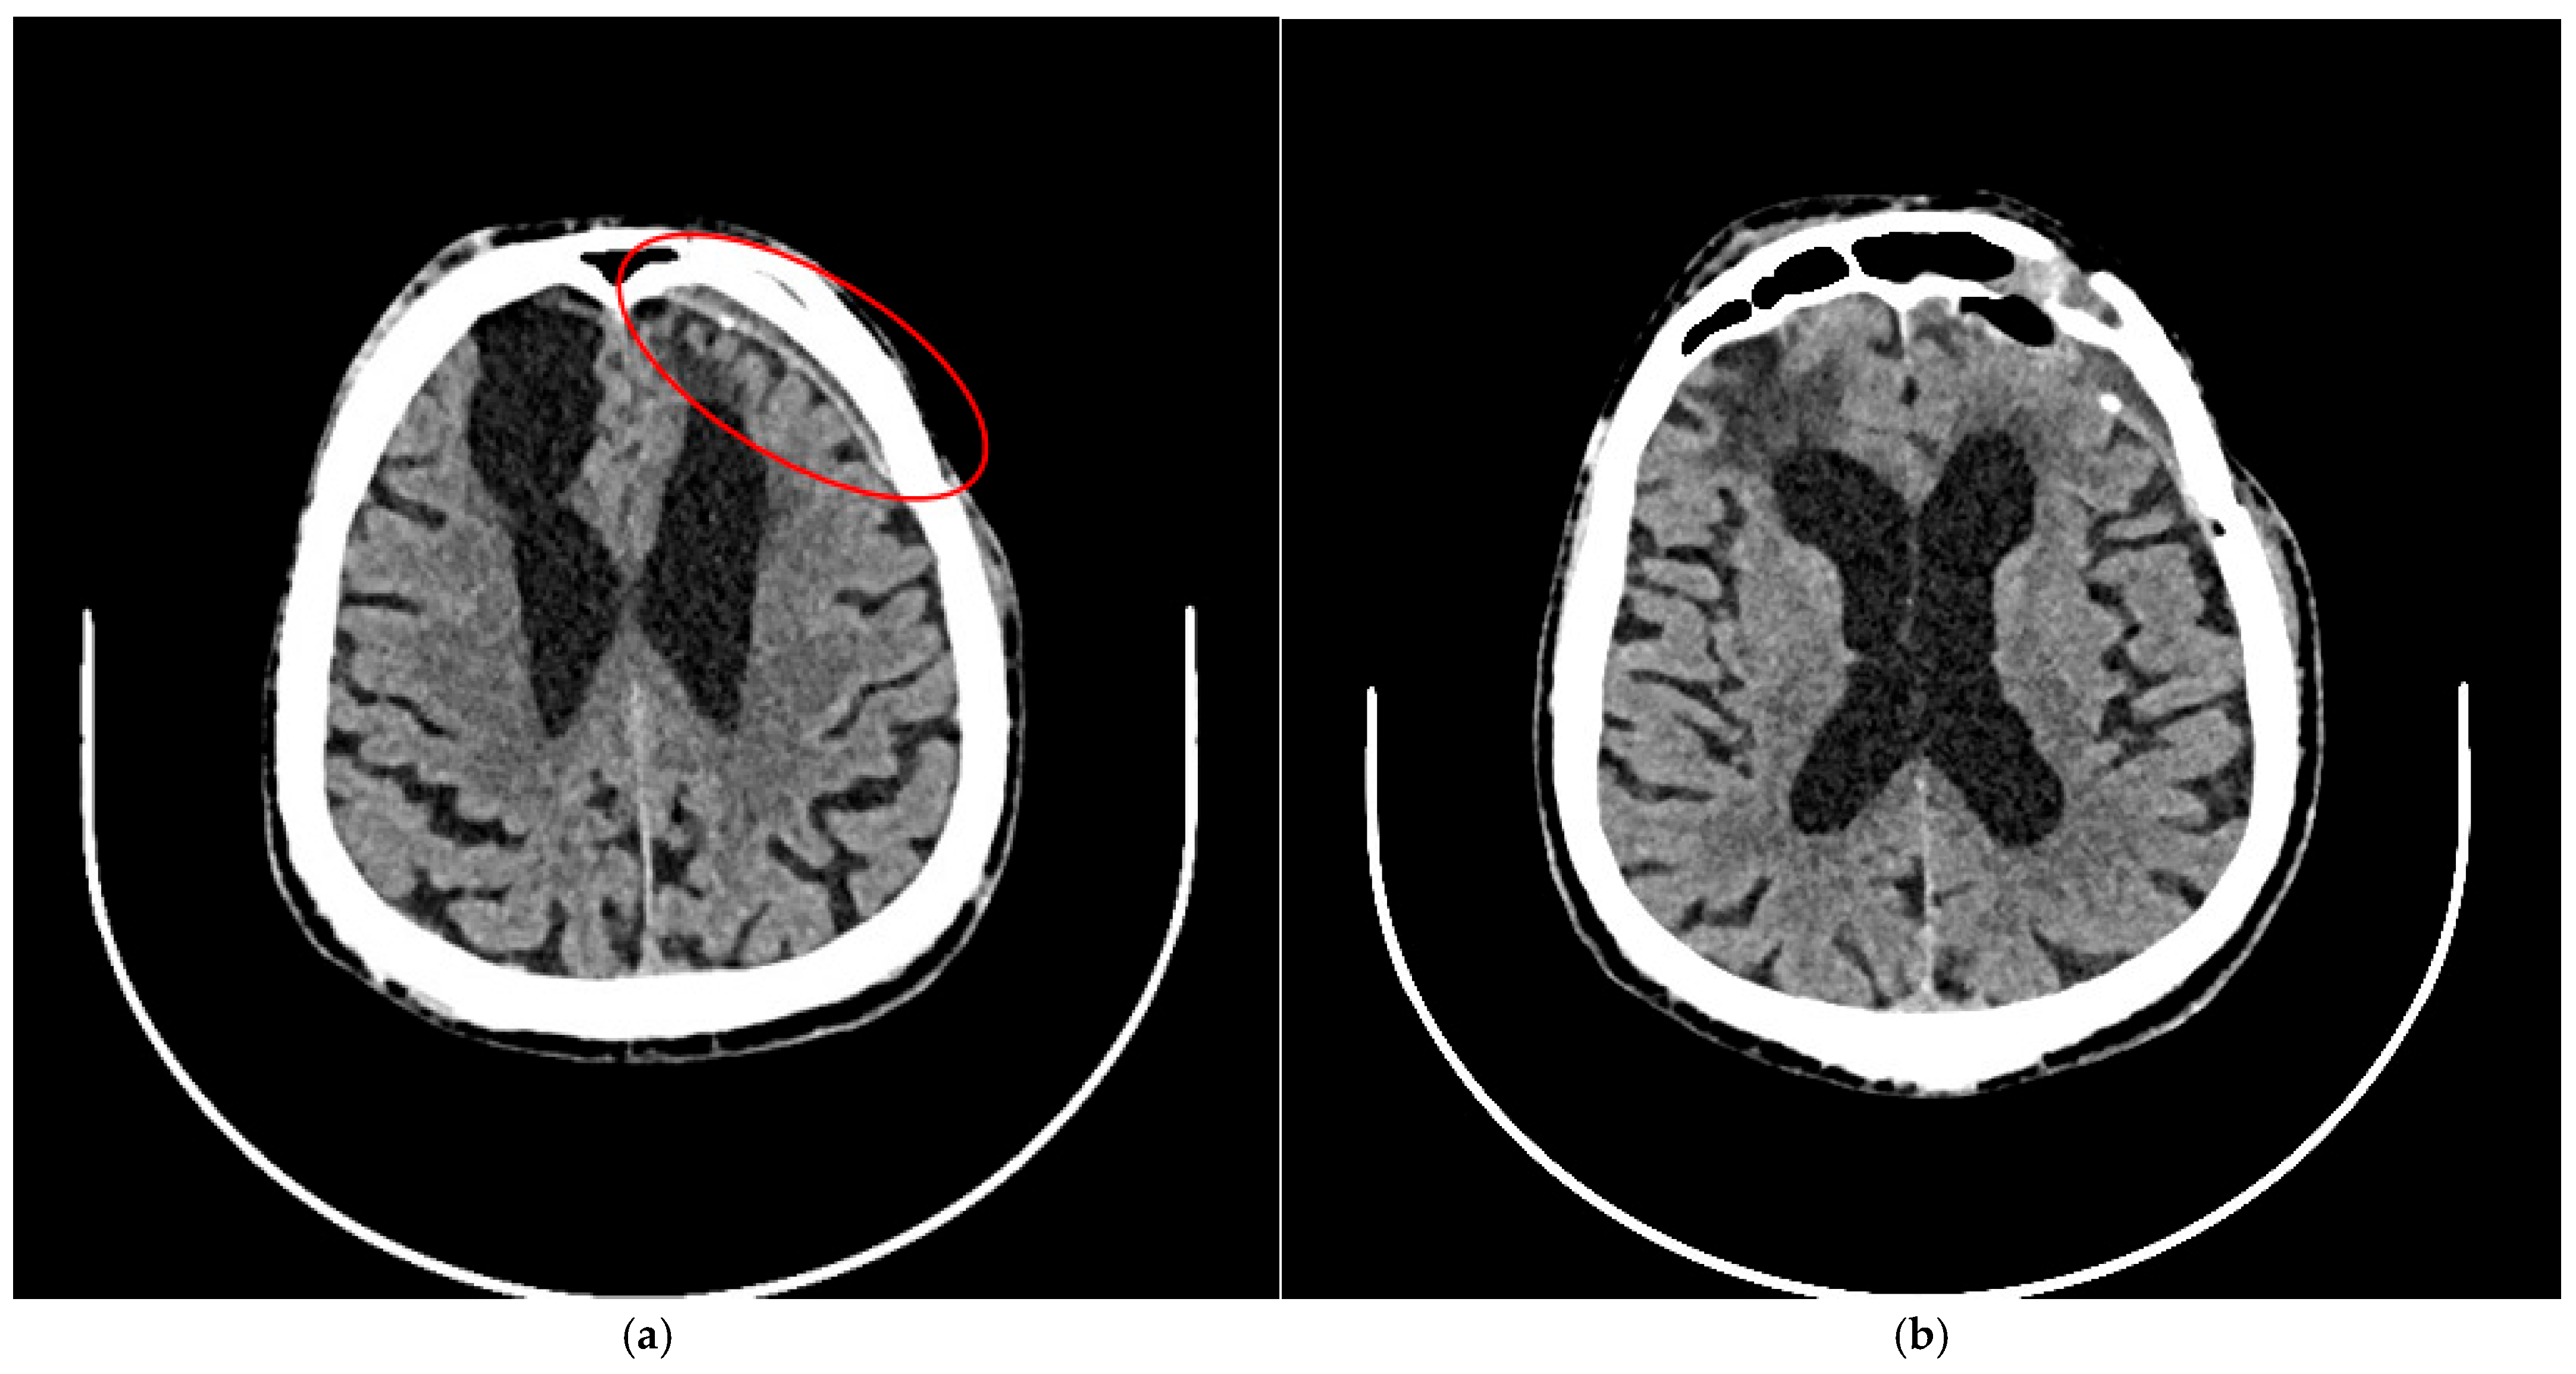

Figure 4. A follow-up CT scan six months after treatment showed no evidence of new intracranial hemorrhage. (a) A narrow chronic subdural hematoma was noted (red circle). (b) Extensive hypodense post-traumatic changes were observed at the base of both frontal lobes. The ventricular system was significantly enlarged and asymmetrical, with evidence of right-sided retraction. There was no displacement of midline structures.